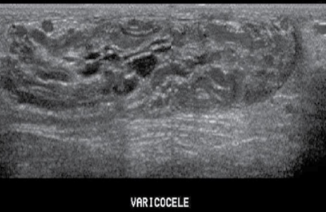

where do varicoceles happen?

at venous pampiniform plexus

measuring vessels is important for diagnosing...

varicocele

what measurement is abnormal meaning there is a varicocele present?

AP over 3mm

when diagnosing ___________________ and ______________________ the valsalva movement is needed

hernia and varicocele

abnormal dilation of veins within the pampiniform- primary caused by incompetent venous valve, secondary caused by increased pressure on sperm vein

varicoceles are more common on the _____________ side

left

causes of varicocele

renal hydronephrosis, abdominal mass, liver cirrhosis, and abdominal malignancy in lt renal vein may cause noncompressible veins

sono appearance of varicocele

less than 2 mm diameter, numerous tortuous tubes within sperm cord, tend to increase in response to Valsalva maneuver